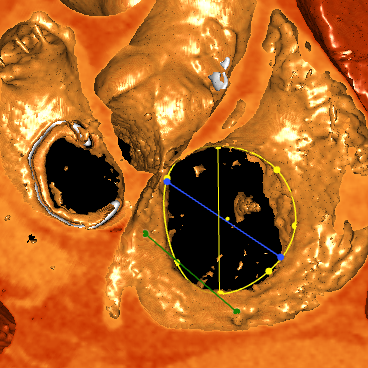

术前CTA

经过术前分析,患者的手术具有很大的挑战。不仅有曾经开胸手术史,右冠的整个后瓣环区有一个支架,给手术带来了很大的难度。经过潘湘斌教授心脏团队的讨论,决定在后瓣靠近隔瓣的位置,植入K-Clip®,进行后隔瓣环的缩环成形,以期改善反流。